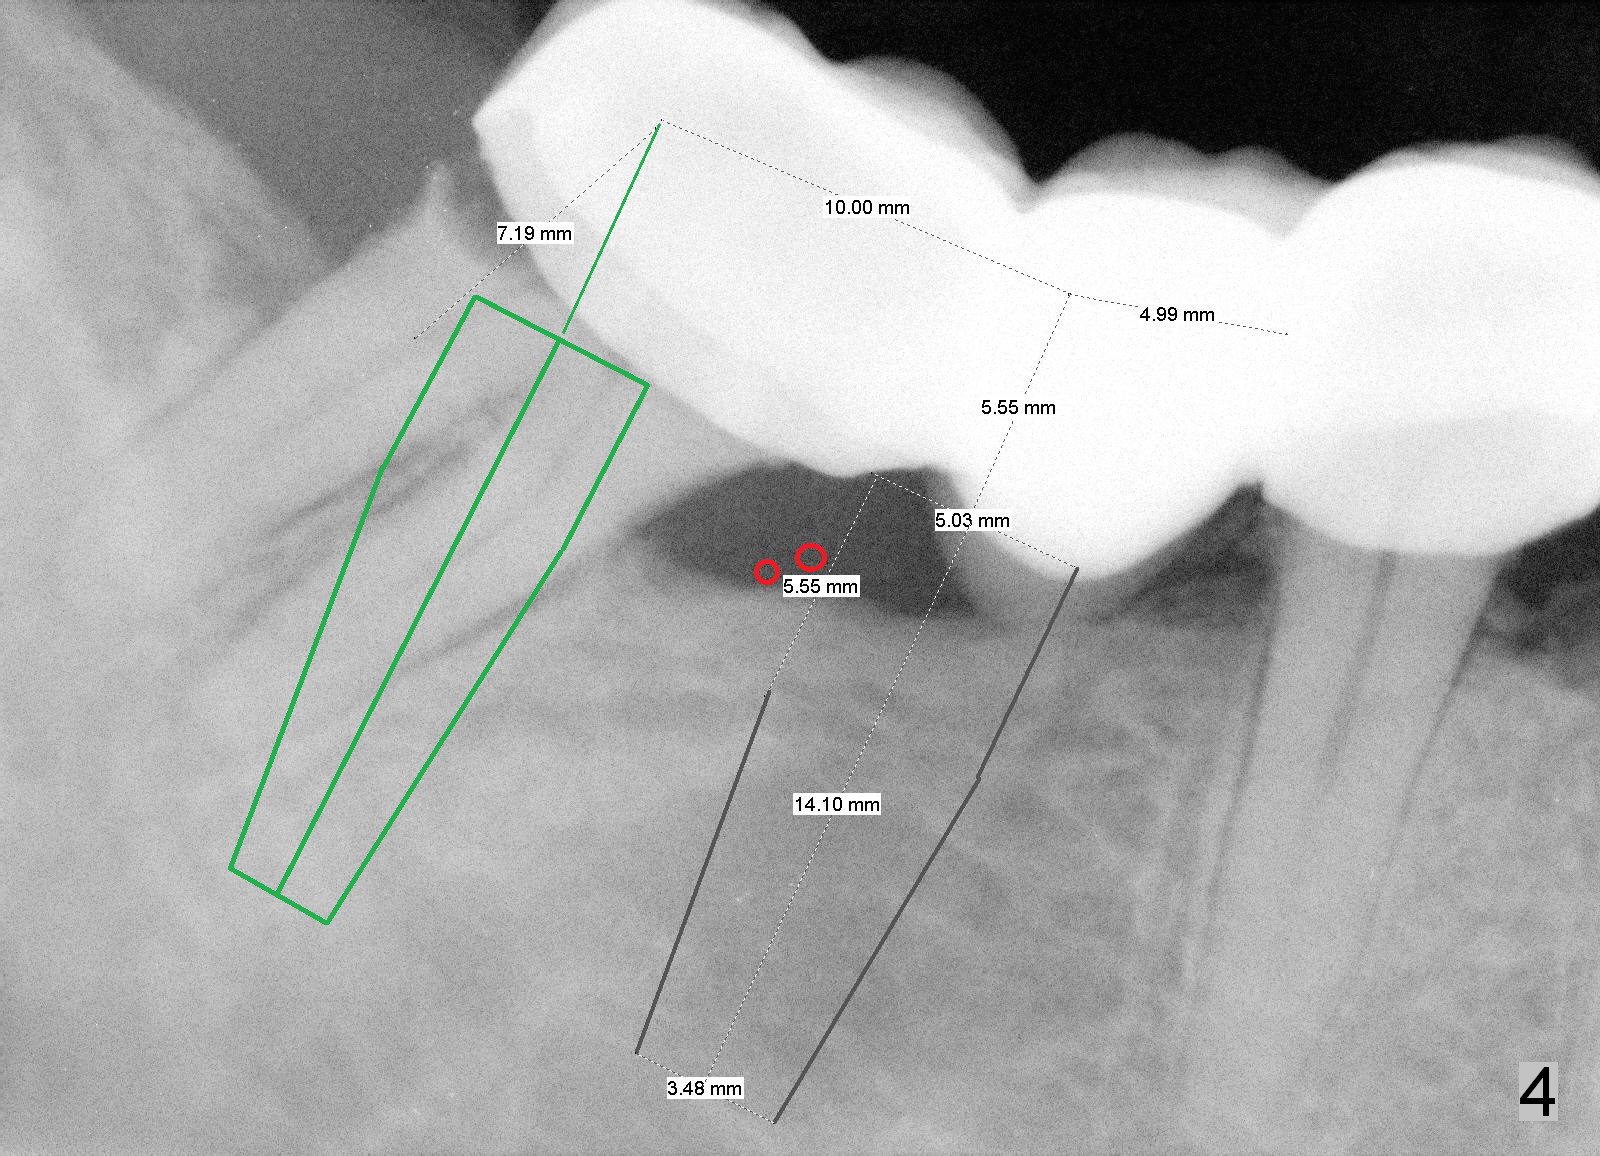

A 43-year-old man has a failed bridge (Fig.1: #29-31). The mesiodistal width of the pontic (#30) is pathologically narrow. When an implant is placed at the site, the osteotomy position should be moved distally, 5 mm from the distal surface of the tooth #29 (Fig.3), while the center of the osteotomy at the site of #31 should be 10 mm from the center of the osteotomy at the 1st molar.

Therefore, it is safer to place an implant coronal to the white arrowheads, i.e., 2 mm apical to the apex of the mesial socket (compare Fig.2,3).

The length of tissue-level implants should be confined to 14 mm (Fig.4).

To ensure the position and trajectory of these 2 implants, impression will be taken prior to surgery for wax up and surgical stent fabrication.